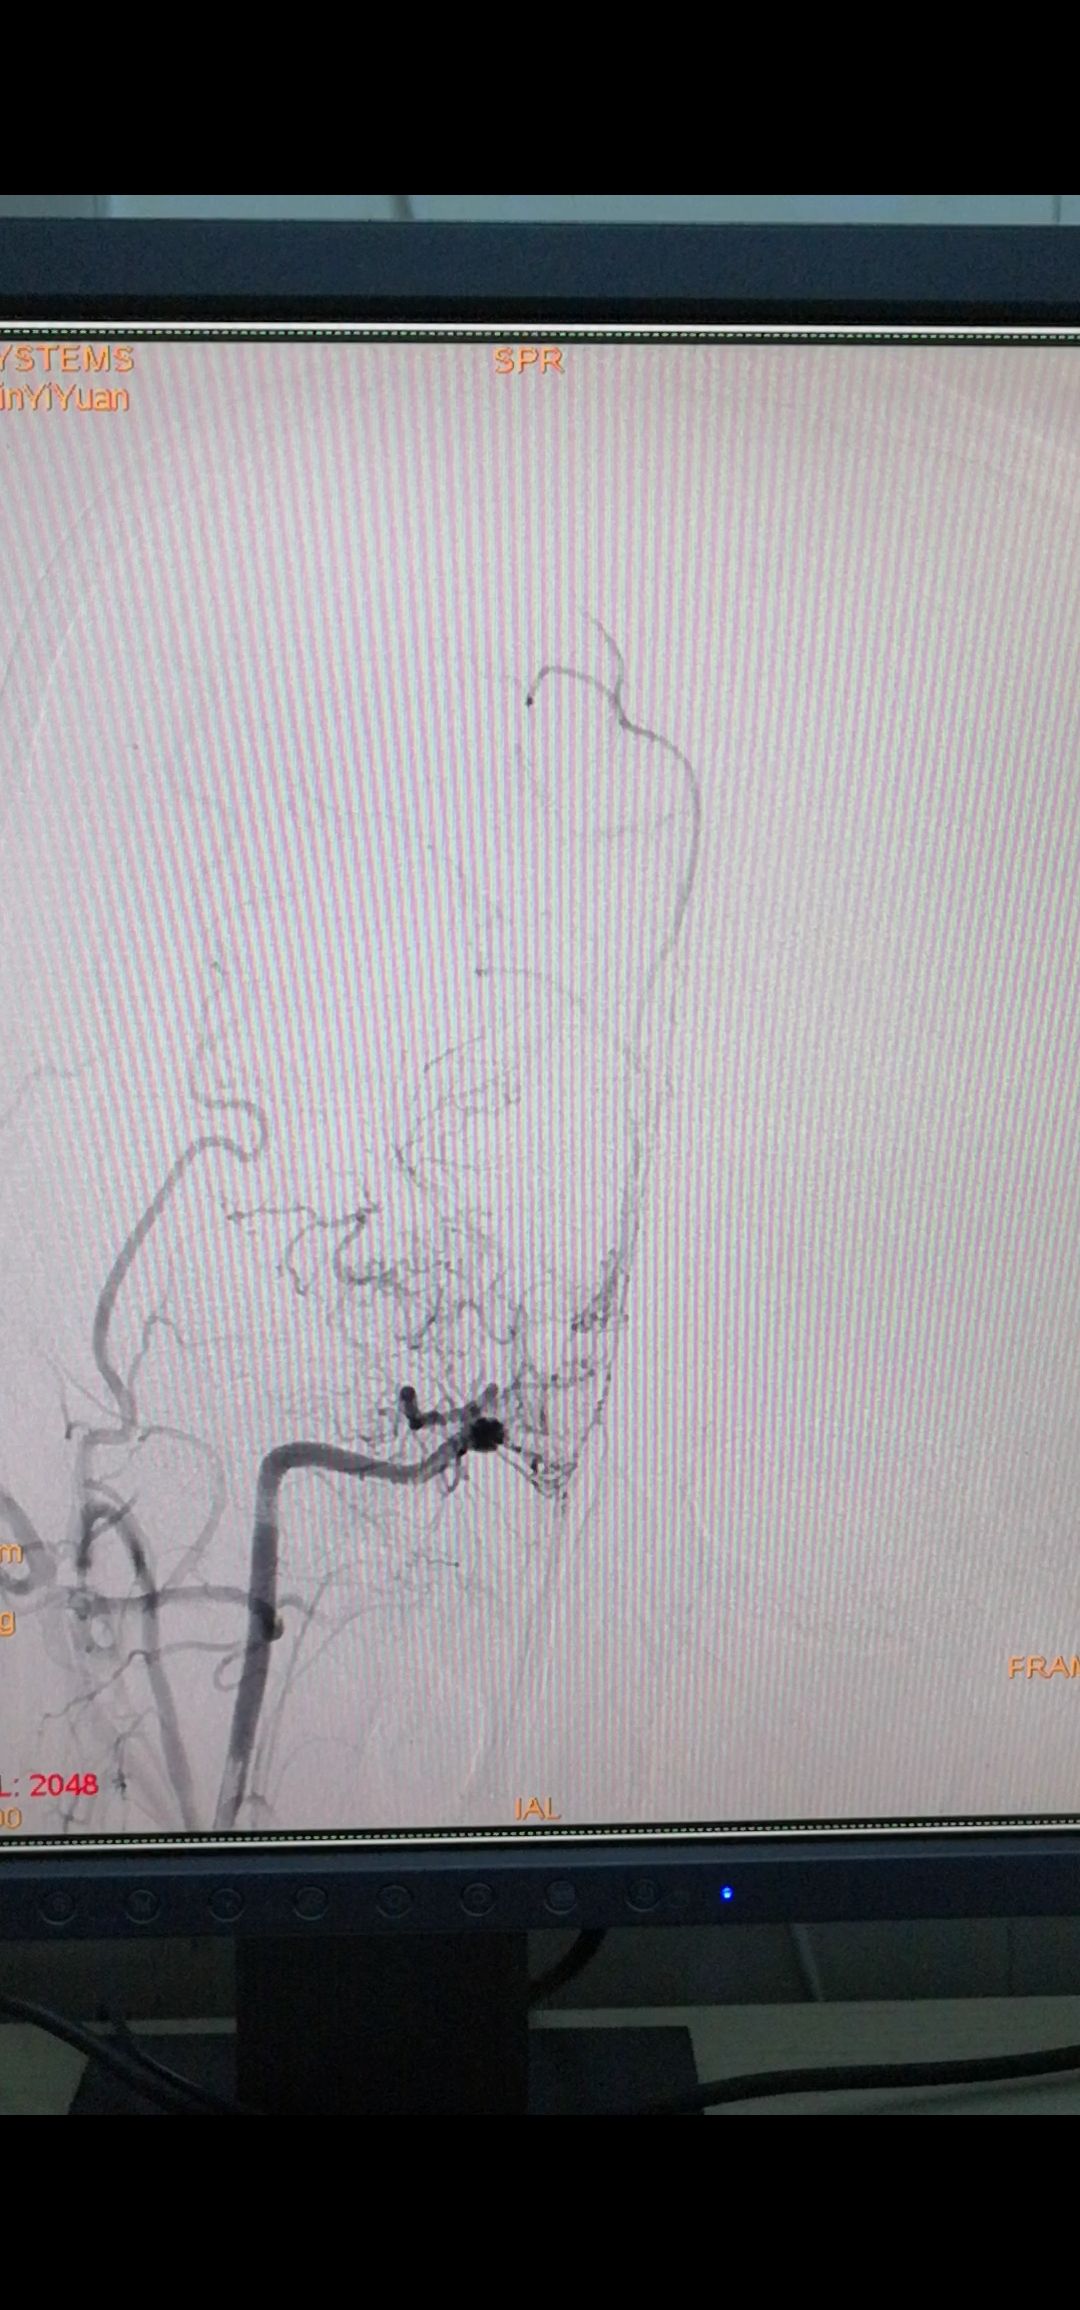

侧位

颈外动脉